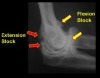

영상 검사

관절의 구조와 연골의 상태, 움직임을 방해하는 내고정물 여부, 이소성 골형성(heterotopic ossification), 골절의 유합여부를 평가합니다.